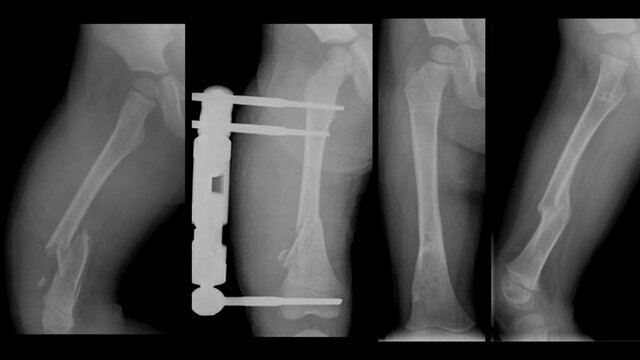

• ACCIDENTE DE TRÀNSITO

ACCIDENTE DE TRÀNSITO

Cuando tenia 10 años sufrí un accidente de transito mientras me trasladaba del cantón El Chaco a la ciudad de Ambato. El bus donde iba por rebasar un bache ejecuto un movimiento brusco que me termino fracturando el fémur izquierdo. Ese evento lo detesto porque tengo recuerdos muy amargos.